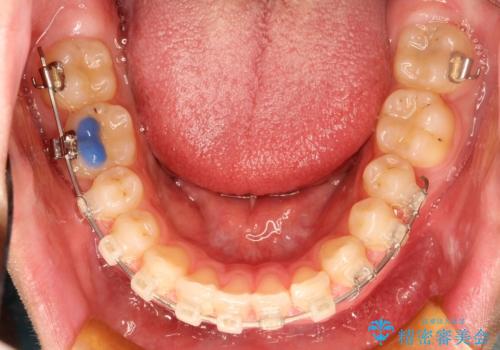

初診時の歯並びの状態としては、上下ともに前歯部の中等度のがたつきがあり、前歯には正中離開があり過蓋咬合を呈してい状態でした。

また奥歯の噛み合わせのズレもあり、特に左は顕著に認められました。

検査の結果、抜歯なし/ワイヤー矯正にて治療を行いました。

また、成長期終盤の男の子だったため成長の余力(下顎を前に牽引んし成長を促進する)を期待しアドバンシンクという装置を使い、下顎の骨の成長を利用した矯正治療を行いました。